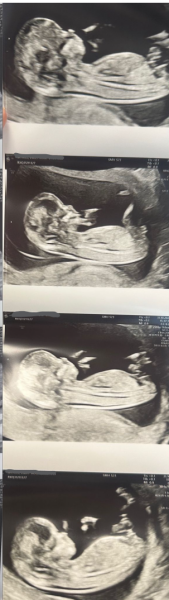

Marym99 · 27/01/2026 03:28

Can you guess the baby by nub theory and skull prediction, I'm in 12 weeks + 4 days

Nub theory prediction wrong?

ColleenRua · 27/01/2026 13:21

That’s a boy I reckon! I can see some stacking at its angling up from the spine